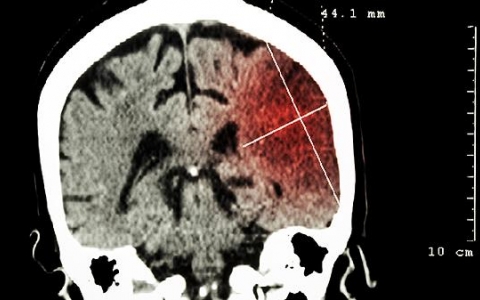

脑梗死应该如何进行治疗

脑梗死患者可以通过药物、手术等方法治疗,在病情稳定后,还需要重视恢复期的治疗。脑梗死可能是大动脉粥样硬化、心源性栓塞等原因导致,患者会出现局灶性神经功能缺损,可